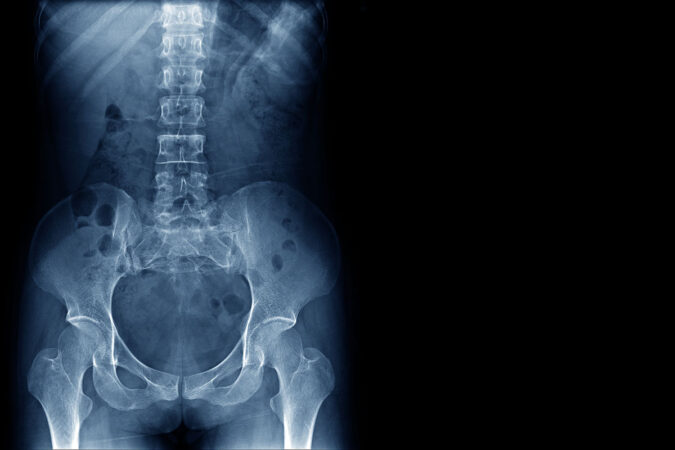

If you have been diagnosed with an annular tear, you most likely have undergone a range of tests at your doctor’s office, including a thorough physical, an X-ray, and an…